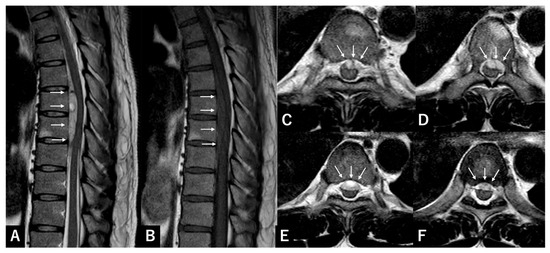

Reliability of Preoperative MRI Findings for Differentiating Spontaneous Spinal Subdural and Epidural Hematomas: A Multi-Institutional Retrospective Study of 27 Surgically Treated Cases

by

Shun Okuwaki, Hiroshi Takahashi, Katsuya Nagashima, Tomoyuki Asada, Takane Nakagawa, Takahiro Sunami, Yosuke Ogata, Kotaro Sakashita, Hisanori Gamada, Kousei Miura, Hiroshi Noguchi, Yosuke Takeuchi, Toru Funayama, Masao Koda and Masaki Tatsumura

J. Clin. Med. 2026, 15(7), 2602; https://doi.org/10.3390/jcm15072602 (registering DOI) - 29 Mar 2026

Abstract

Background/Objectives: Spontaneous spinal subdural hematoma (SSSDH) is a rare and severe condition that causes rapid neurological decline. Spontaneous spinal epidural hematoma (SSEH) presents similarly but is more common, and surgical management differs because SSSDH requires an intradural approach. Few studies have assessed the

[...] Read more.

Background/Objectives: Spontaneous spinal subdural hematoma (SSSDH) is a rare and severe condition that causes rapid neurological decline. Spontaneous spinal epidural hematoma (SSEH) presents similarly but is more common, and surgical management differs because SSSDH requires an intradural approach. Few studies have assessed the reliability of magnetic resonance imaging (MRI) features used to distinguish SSSDH from SSEH in patients requiring surgery. Methods: We retrospectively reviewed 27 patients who underwent surgical evacuation of spinal hematomas at two institutions (2015–2025). Definitive hematoma location was determined intraoperatively. Four MRI features—shape (crescentic vs. biconvex), location (ventral vs. dorsal), craniocaudal length (<5 vs. ≥5 segments), and spinal region—were independently evaluated by two reviewers. Inter- and intra-rater reliability was assessed using agreement rate and Cohen’s kappa (κ) with 95% confidence intervals (95% CIs). Results: Among 27 cases, three (11.1%) were SSSDH and 24 were SSEH. Hematoma location, length, and spinal region demonstrated perfect inter- and intra-rater agreement (κ = 1.00). For hematoma shape, intra-rater agreement was good (96.2%, κ = 0.84; 95% CI 0.52–1.00), whereas inter-rater agreement was poor to fair (84.6%, κ = 0.26; 95% CI −0.25–0.77). Notably, two of the three SSSDHs demonstrated a biconvex configuration, and 83.3% of SSEHs also exhibited a biconvex morphology. Conclusions: MRI features such as hematoma location, extent, and spinal level were highly reproducible, whereas hematoma shape showed limited reliability. Although ventral hematomas most strongly suggest SSSDH, atypical SSEH presentations occur. When dorsal exposure reveals no epidural hematoma, intradural exploration should be promptly considered.

Full article

(This article belongs to the Special Issue Clinical Advances in Spinal Neurosurgery)